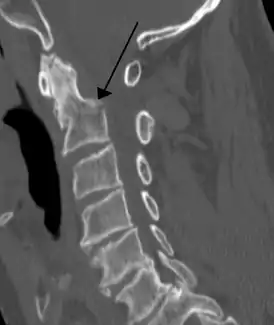

![]() Спиральная компьютерная томограмма перелома основания зубовидного отростка (тип II) со смещением | |

- При типе II (более 60 %) линия перелома расположена на границе зубовидного отростка и тела позвонка[2].